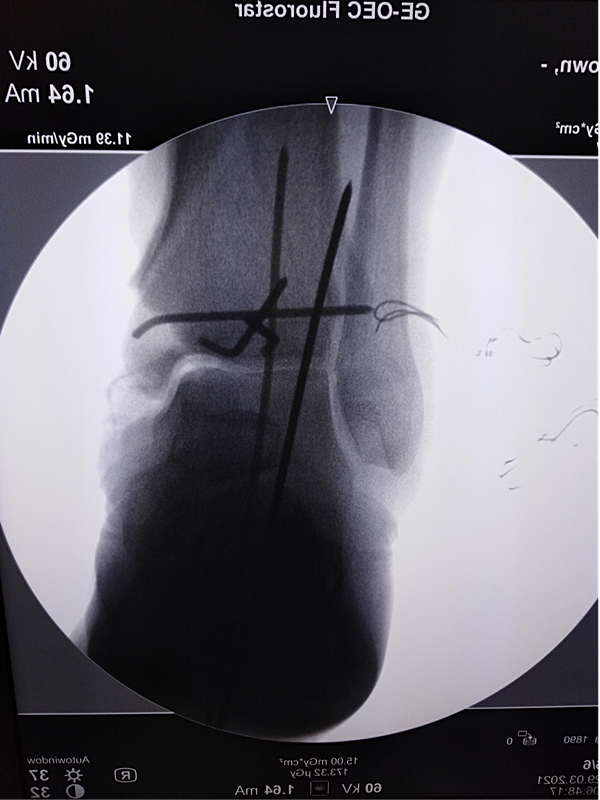

第三次手术图片

第三次清创+骨折复位螺钉内固定+内踝重建+Ilizarov环形外固定固定+VSD负压引流手术